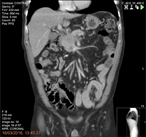

An incredibly dilated Wirsung mimicking a sero-cystic neoplasm of the pancreatic head

Contardo Vergani and others

Journal of Surgical Case Reports, Volume 2018, Issue 6, June 2018, rjy122, https://doi.org/10.1093/jscr/rjy122